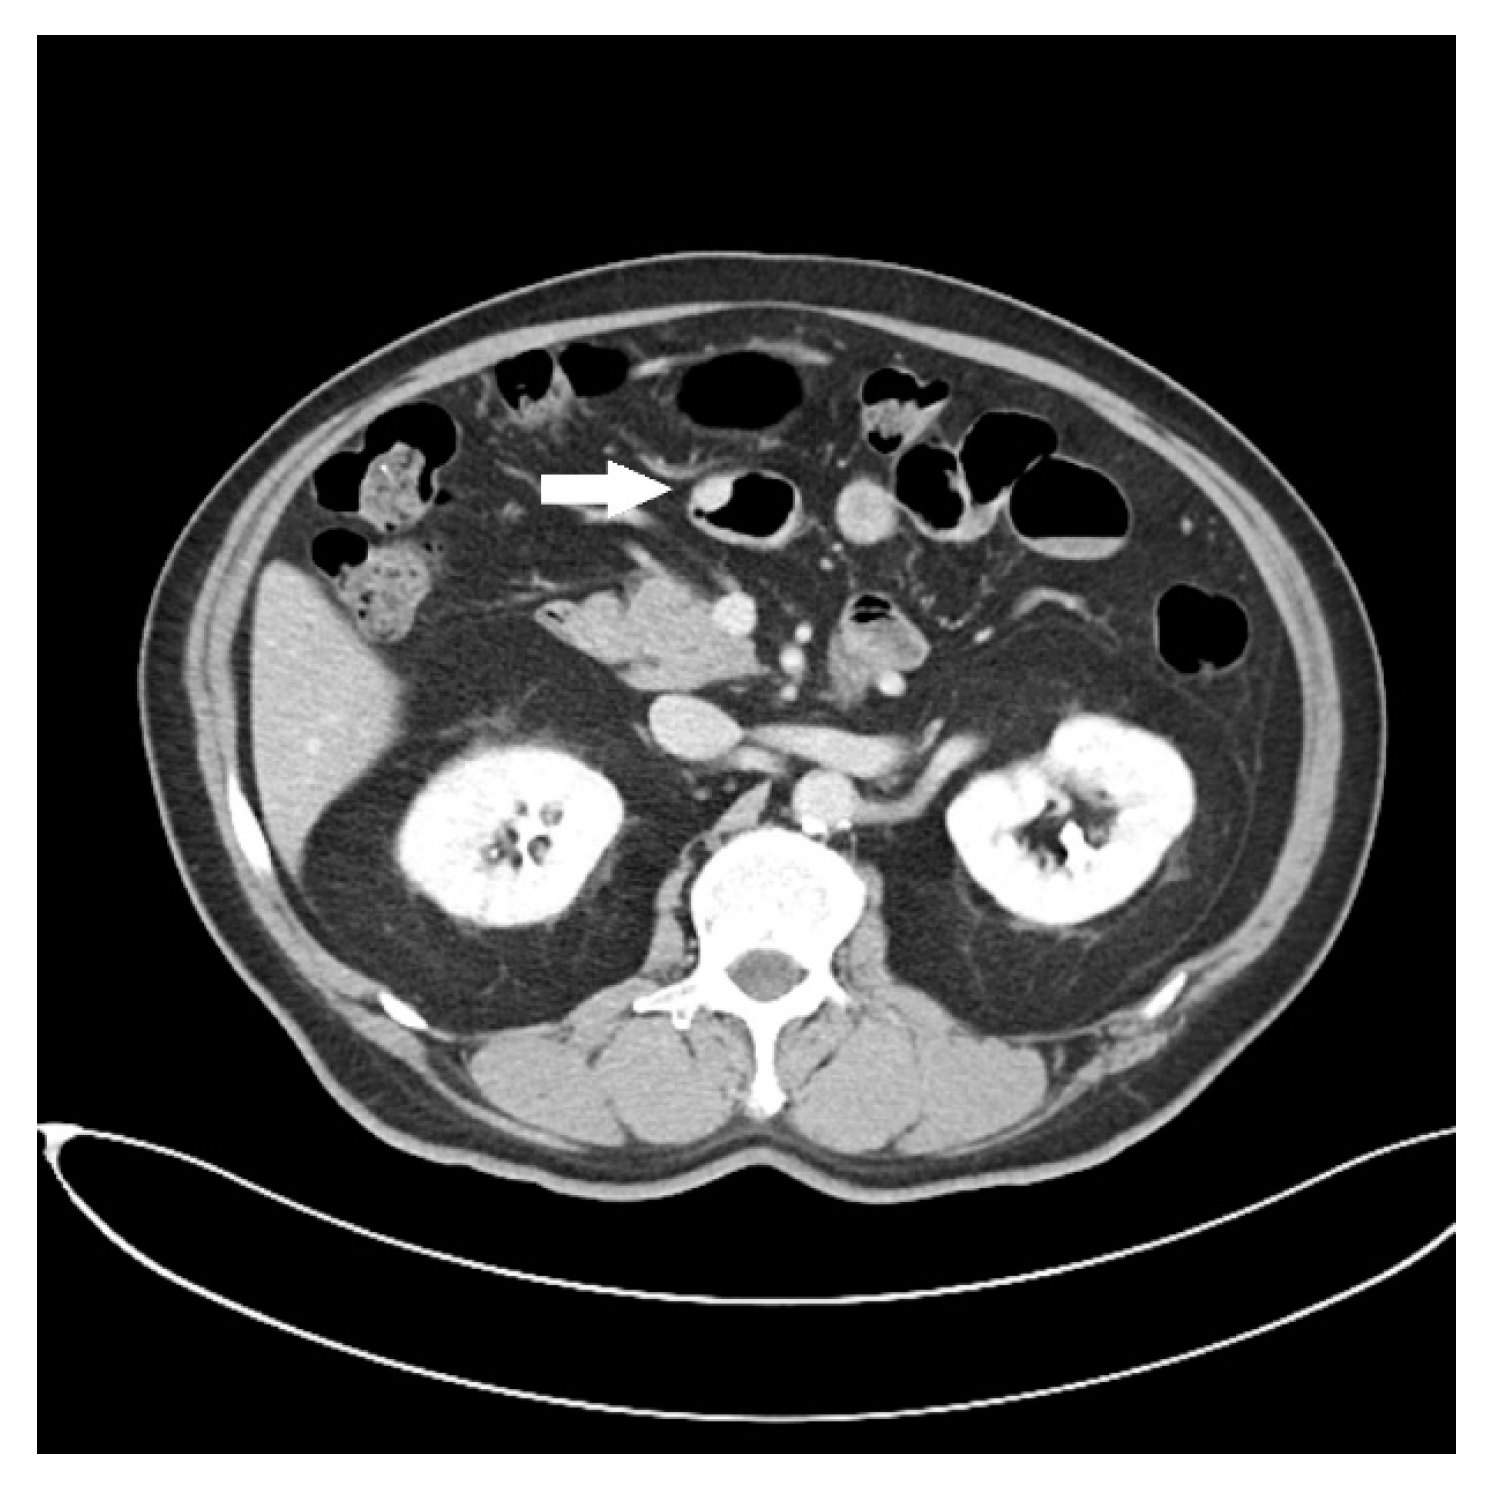

Endoscopic Ultrasound Appearance of Jejunal Ectopic Pancreas Mimicking Metastatic Nodule in a Cancer Patient